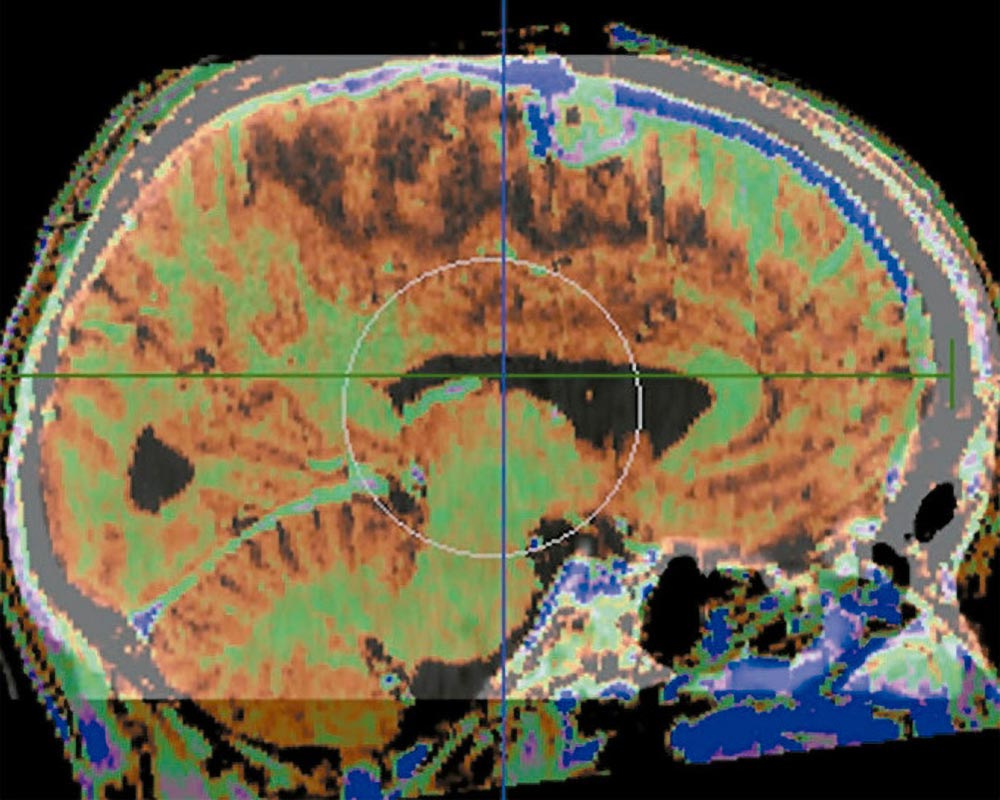

Es un avanzado sistema que fusiona información anatómica obtenida de TAC y RMN potenciando la visualización y localización de las estructuras de interés.

Es indispensable que, antes de la administración de IMRT al paciente, se controlen y verifiquen cada uno de los campos de Intensidad Modulada. Para ello, es necesario comparar las distribuciones de dosis obtenidas con el sistema IMRT con imágenes adquiridas en las condiciones de tratamiento.

Centro Médico Privado “Deán Funes” ha incorporado un scanner digital y un software capaz de interpretar los datos para la validación del plan de Radioterapia de Intensidad Modulada. Además se requiere efectuar comprobaciones independientes de las dosis absolutas mediante el uso de cámaras de ionización y fantomas diseñados para IMRT.